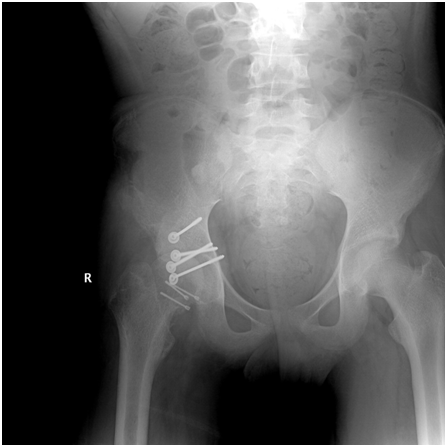

X -ray dislocation hip with false acetabulum

Diagnosis neglected dislocation hip with false articulation head femur with iliac bone. Skeletal traction is done for 3 days by 12 kg then I did posterior approach right hip with exploration and isolation sciatic nerve.

Figure 2 Neglected Fracture Dislocation Hip 2.